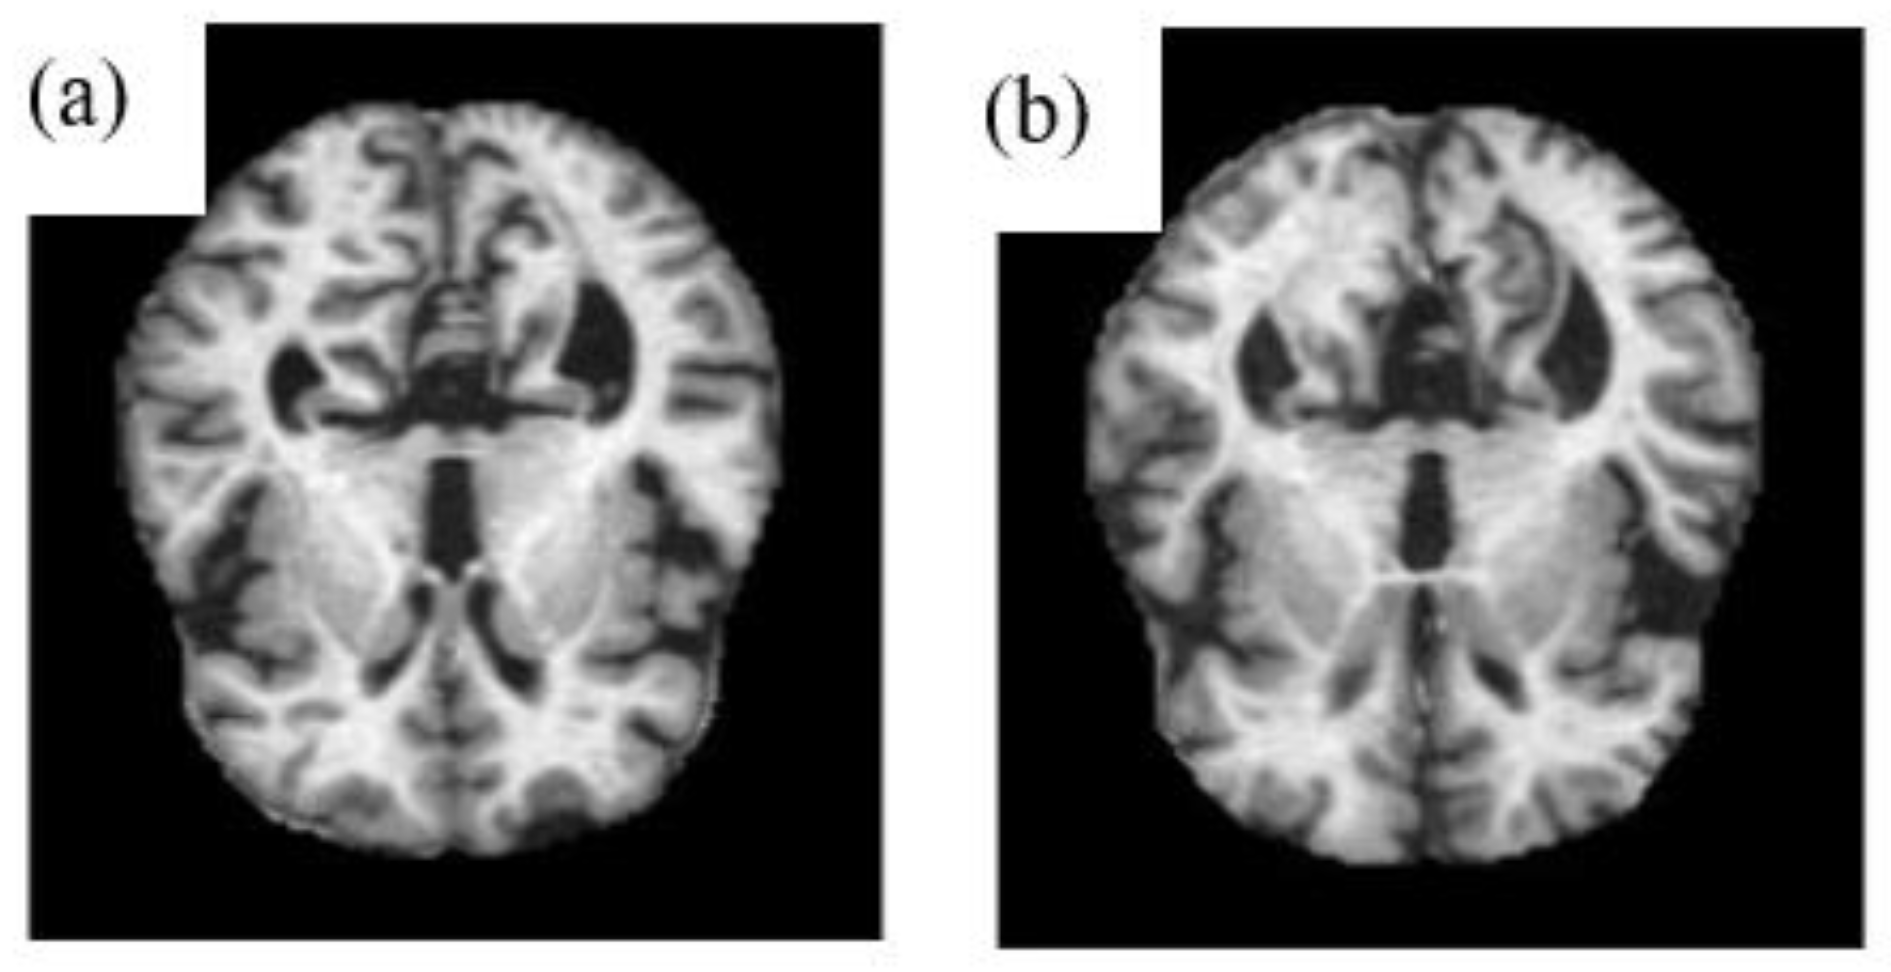

2.1. Pre-Processing